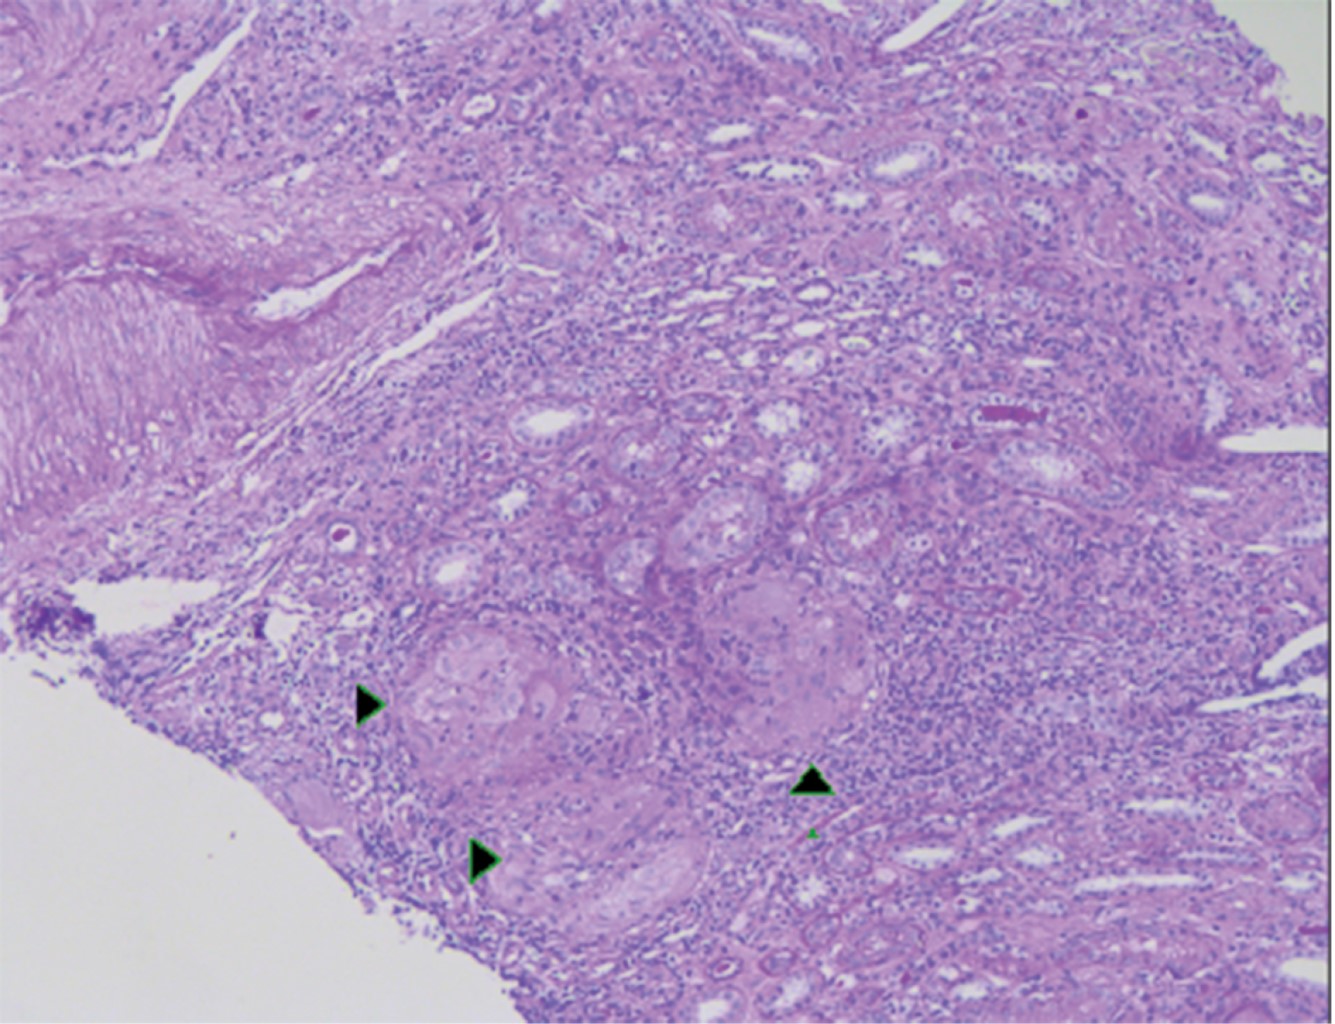

La biopsia renal mostró una nefritis granulomatosa tubulointersticial no caseificante con esclerosis global focal y datos anatómicos de arteriopatía hipertensiva (Figuras 4, 5 y 6).

El hallazgo más frecuente es la nefritis granulomatosa tubulointersticial no caseificante,20,41 documentada por biopsia en el caso 1.

Figura 4

Figura 5

Figura 6